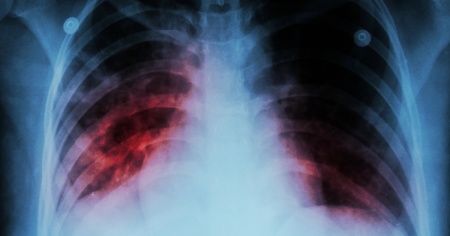

Tubercolosi, casi in crescita anche in Svizzera

La malattia continua a mietere ogni anno più di un milione di vittime in tutto il mondo. Nel 2025 i casi sono aumentati anche nel nostro Paese.

ZURIGO - Nella privilegiata Svizzera molti pensano che la tubercolosi appartenga al passato, ma la realtà è ben diversa: dopo una breve parentesi in cui il COVID-19 è stato la malattia infettiva più mortale al mondo, ora il primato è tornato alla tubercolosi.

Sebbene da decenni esistano trattamenti efficaci, la malattia continua a mietere ogni anno più di un milione di vittime in tutto il mondo. Nel 2025 i casi sono aumentati anche nel nostro Paese.